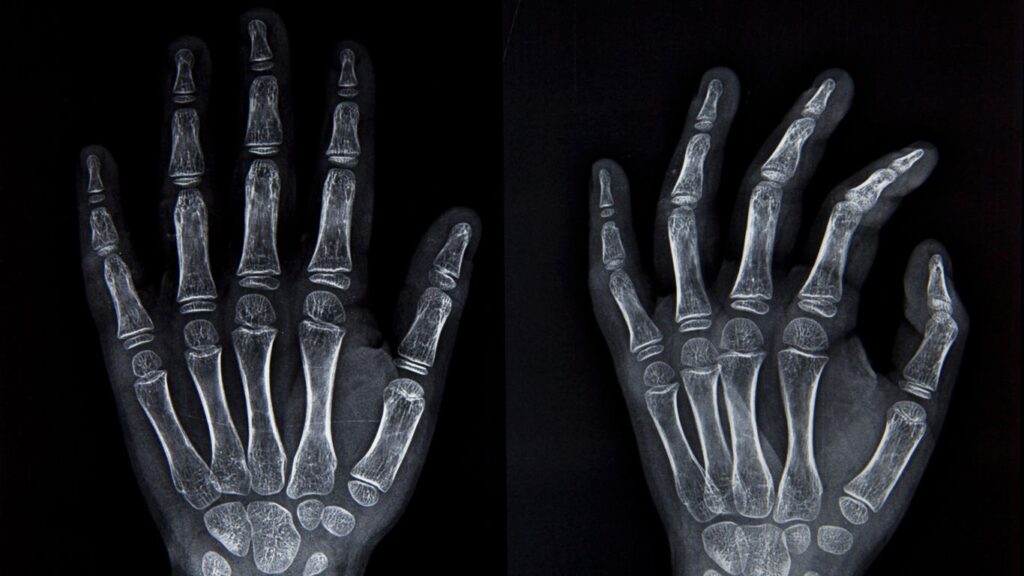

Radiografías en Querétaro – Precisión y Rapidez en Altaria

En Altaria, estamos comprometidos a ofrecer un servicio de Radiografías en Querétaro que se destaca por su velocidad y precisión en el diagnóstico médico. Utilizamos tecnología de vanguardia para garantizar que obtenemos imágenes de alta calidad, lo que permite un análisis detallado para una atención adecuada. Además, nuestra digitalización acelera el proceso, asegurando que los resultados […]